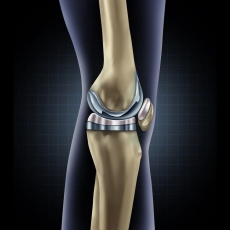

• Χειρουργικής Γόνατος, με έμφαση στην αρθροσκόπηση και ολική αρθροπλαστική

Συμμετείχε σε ετήσια βάση, σε διεθνή ιατρικά συνέδρια όπως επίσης και σε πτωματικά σεμινάρια για την εκμάθηση νέων χειρουργικών τεχνικών. Εξειδικεύτηκε στη διάγνωση και αντιμετώπιση παθήσεων και κακώσεων με ιδιαίτερη έμφαση στη αρθροσκοπική τεχνική και την αρθροπλαστική. Σημαντικό μέρος της πρακτικής του αποτέλεσε και το ορθοπαιδικό τραύμα όπως τα κατάγματα και οι αθλητικές κακώσεις καθώς εργάστηκε ως επιμελητής ειδικός Χειρουργός σε Τριτοβάθμια Νοσοκομεία και Μείζονα Κέντρα αναφοράς Τραύματος ενεργό μέλος πολυδύναμων ιατρικών ομάδων.